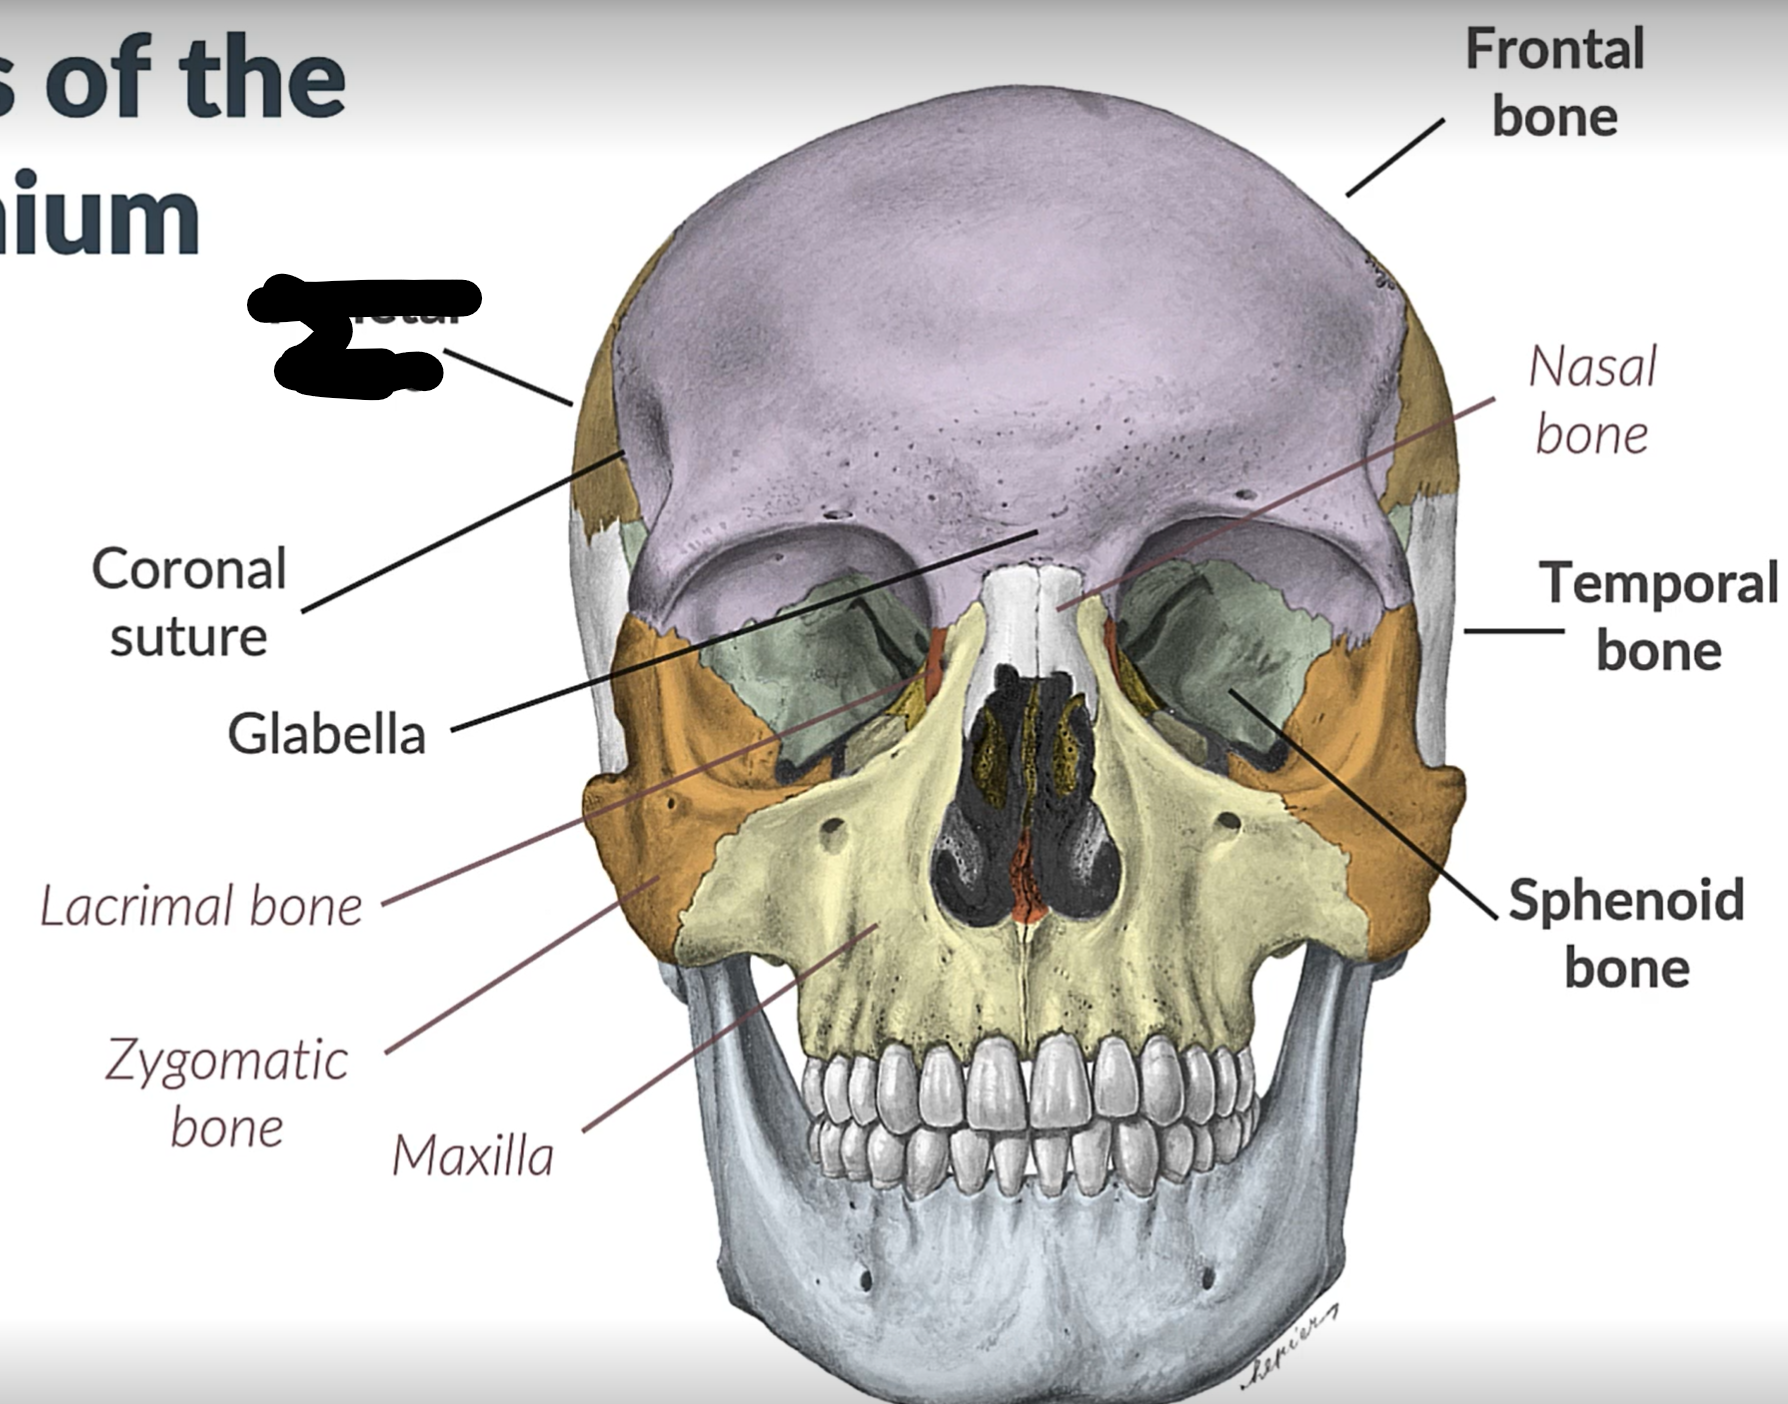

Parietal bone

Frontal bone

Temporal bone

Sphenoid bone

Zygomatic bone

Lacrimal bone

Coronal suture

Maxilla